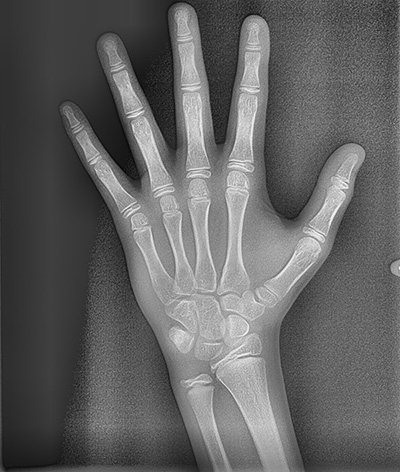

측모, 정면 및 수완부(손) 엑스레이 및 CT 촬영

옆얼굴 뿐만 아니라 정면 얼굴 엑스레이와 어린이들의 경우 현재 성장단계는 어떠한지 알기 위하여 손사진도 같이 촬영합니다. CT 촬영이 필요한 경우에는 추가로 CT 촬영도 하게 되지요.

성장단계 검사

뷰노매드 본에이지 성장판 검사

아이들의 경우 추가적으로 성장판 검사도 진행하는데요. 뷰노매드 본에이지 검사는 손 엑스레이 사진을 판독하여 현재의 뼈나이와 예상 신장을 알려주는 검사입니다. 뷰노매드 본에이지는 약 72.5% 정도의 정확성을 갖는 검사로, 의사가 눈으로 판독했을 때보다 판독 일치도는 15% 이상 향상된 프로그램입니다.

요즘 진단을 해보면 어머님들께서 확실히 성장판 검사에 대한 관심이 아주 높더라구요. 아무래도 주변에 성장 주사를 맞는 아이들도 많다보니, 아이들의 키가 어느 정도까지 클지 많이들 궁금해하십니다. 손 엑스레이 사진을 촬영한 후 뷰노매드 본에이지 검사를 시행하여 예상 신장 결과를 정밀 진단때 설명해드리는데 어머님들의 만족도가 아주 높습니다 :) (저도 호기심에 제 아들 손사진을 찍어보았는데 예상키가 191.8cm가 나와서 깜짝 놀랐습니다 ㅎㅎㅎ)

뷰노매드 본에이지 검사 연세정원치과